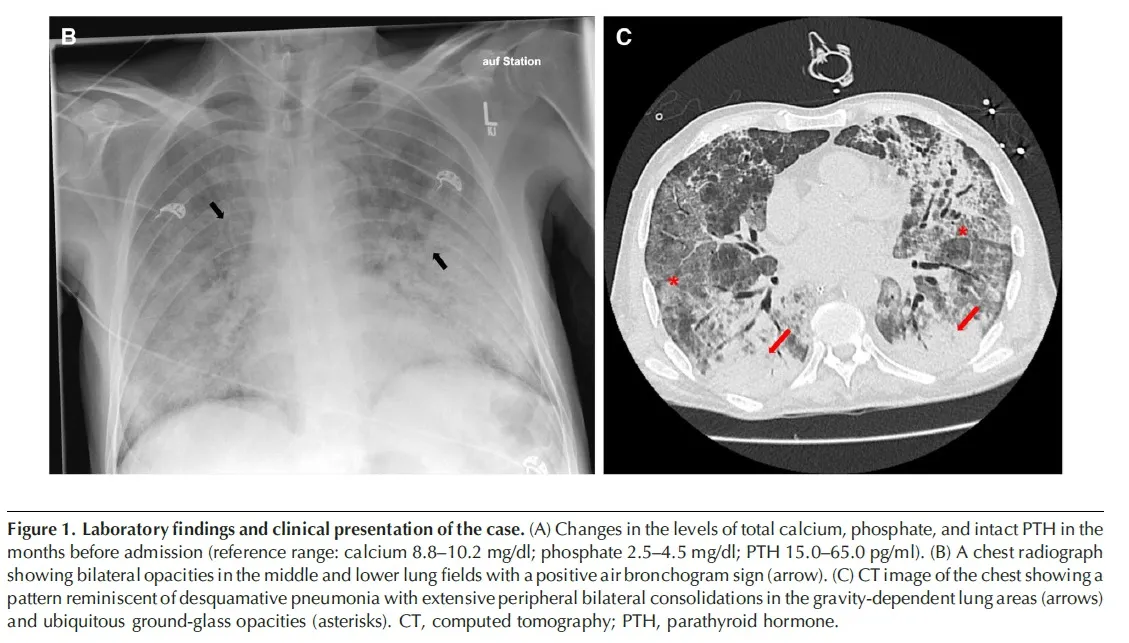

Changes in the levels of total calcium, phosphate, and intact PTH in the months before admission (reference range: calcium 8.8–10.2 mg/dl; phosphate 2.5–4.5 mg/dl; PTH 15.0–65.0 pg/ml).

* A radiografia de tórax mostrou infiltrados no pulmão esquerdo e a tomografia computadorizada revelou consolidações extensas com opacidades em vidro fosco nos lobos inferiores de ambos os pulmões.